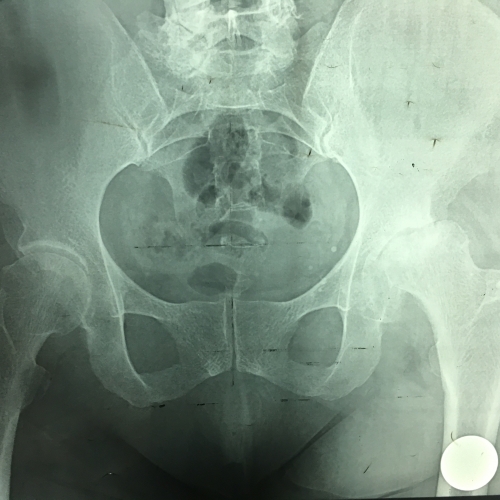

Эндопротезирование тазобедренного сустава